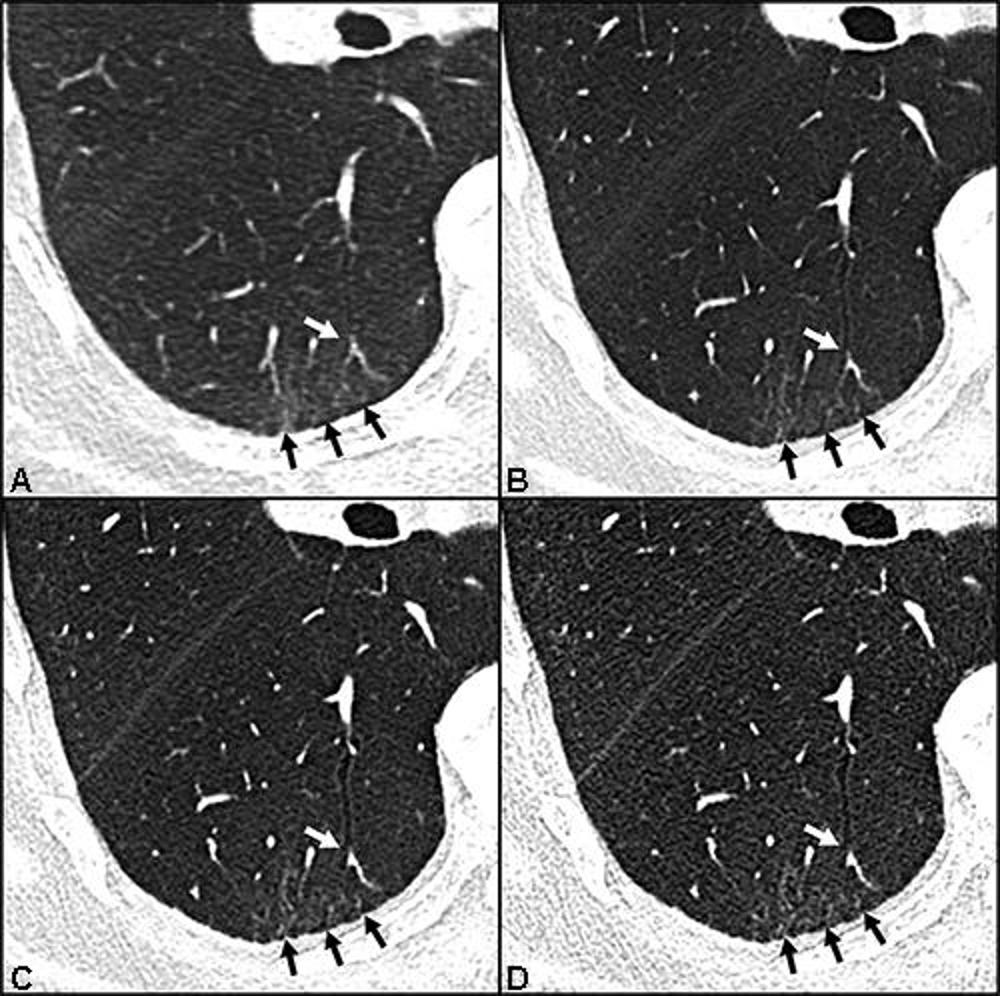

Figure 3. Ultra-high-resolution photon-counting CT reveals reticulations in lung areas classified as ground-glass opacity by high-resolution energy-integrating CT: Axial CT lung images without contrast agent of a 55-year-old man with persistent exertional dyspnea and chronic fatigue 399 days after COVID-19: 1.0mm image obtained with energy-integrating detector (EID) CT (A), and 1mm (B), 0.4mm (C) and 0.2mm (D) images obtained with photon-counting detector CT at the same level. Ground-glass opacities detected by EID CT (black arrows in A) were found to contain reticulations in PCD CT (black arrows in B-D).

High-res (TIF) version